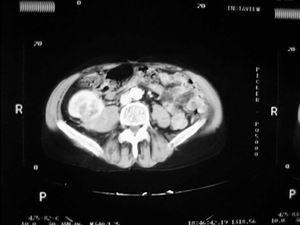

Caso 2. Mujer de 32 años, con insuficiencia renal crónica secundaria a nefropatía IgA, que recibió trasplante renal de cadáver (de un varón) a los 21 años. Por deterioro progresivo de la función renal con creatinina de 3,5 mg/dl y filtrado glomerular estimado de 16 ml/min/1,73 m2 se solicita ecografía que evidencia un nódulo sólido de 32 mm en el tercio superior del injerto. La biopsia practicada confirma la presencia de carcinoma de células renales. La exploración física es normal, la TAC no evidenció signos de extensión tumoral y la paciente estaba asintomática. Dado el mal pronóstico a medio plazo del injerto, se decide practicar una transplantectomía laparoscópica extracapsular, y la paciente volvió a diálisis tras la intervención. El resultado de anatomía patológica fue de carcinoma de células renales tipo papilar de 33 mm limitado al riñón con márgenes libres (pT1a) y glomerulonefritis crónica severa en el resto del riñón (figura 2). Tras 38 meses de seguimiento la paciente está libre de enfermedad. El estudio cromosómico determinó la presencia de cromosoma Y en las células tumorales, confirmando el origen tumoral del donante. Se estudió, asimismo, el otro receptor del mismo donante mediante ecografía abdominal y TAC, sin evidenciar neoformaciones.

Figura 2. Carcinoma de células renales tipo papilar